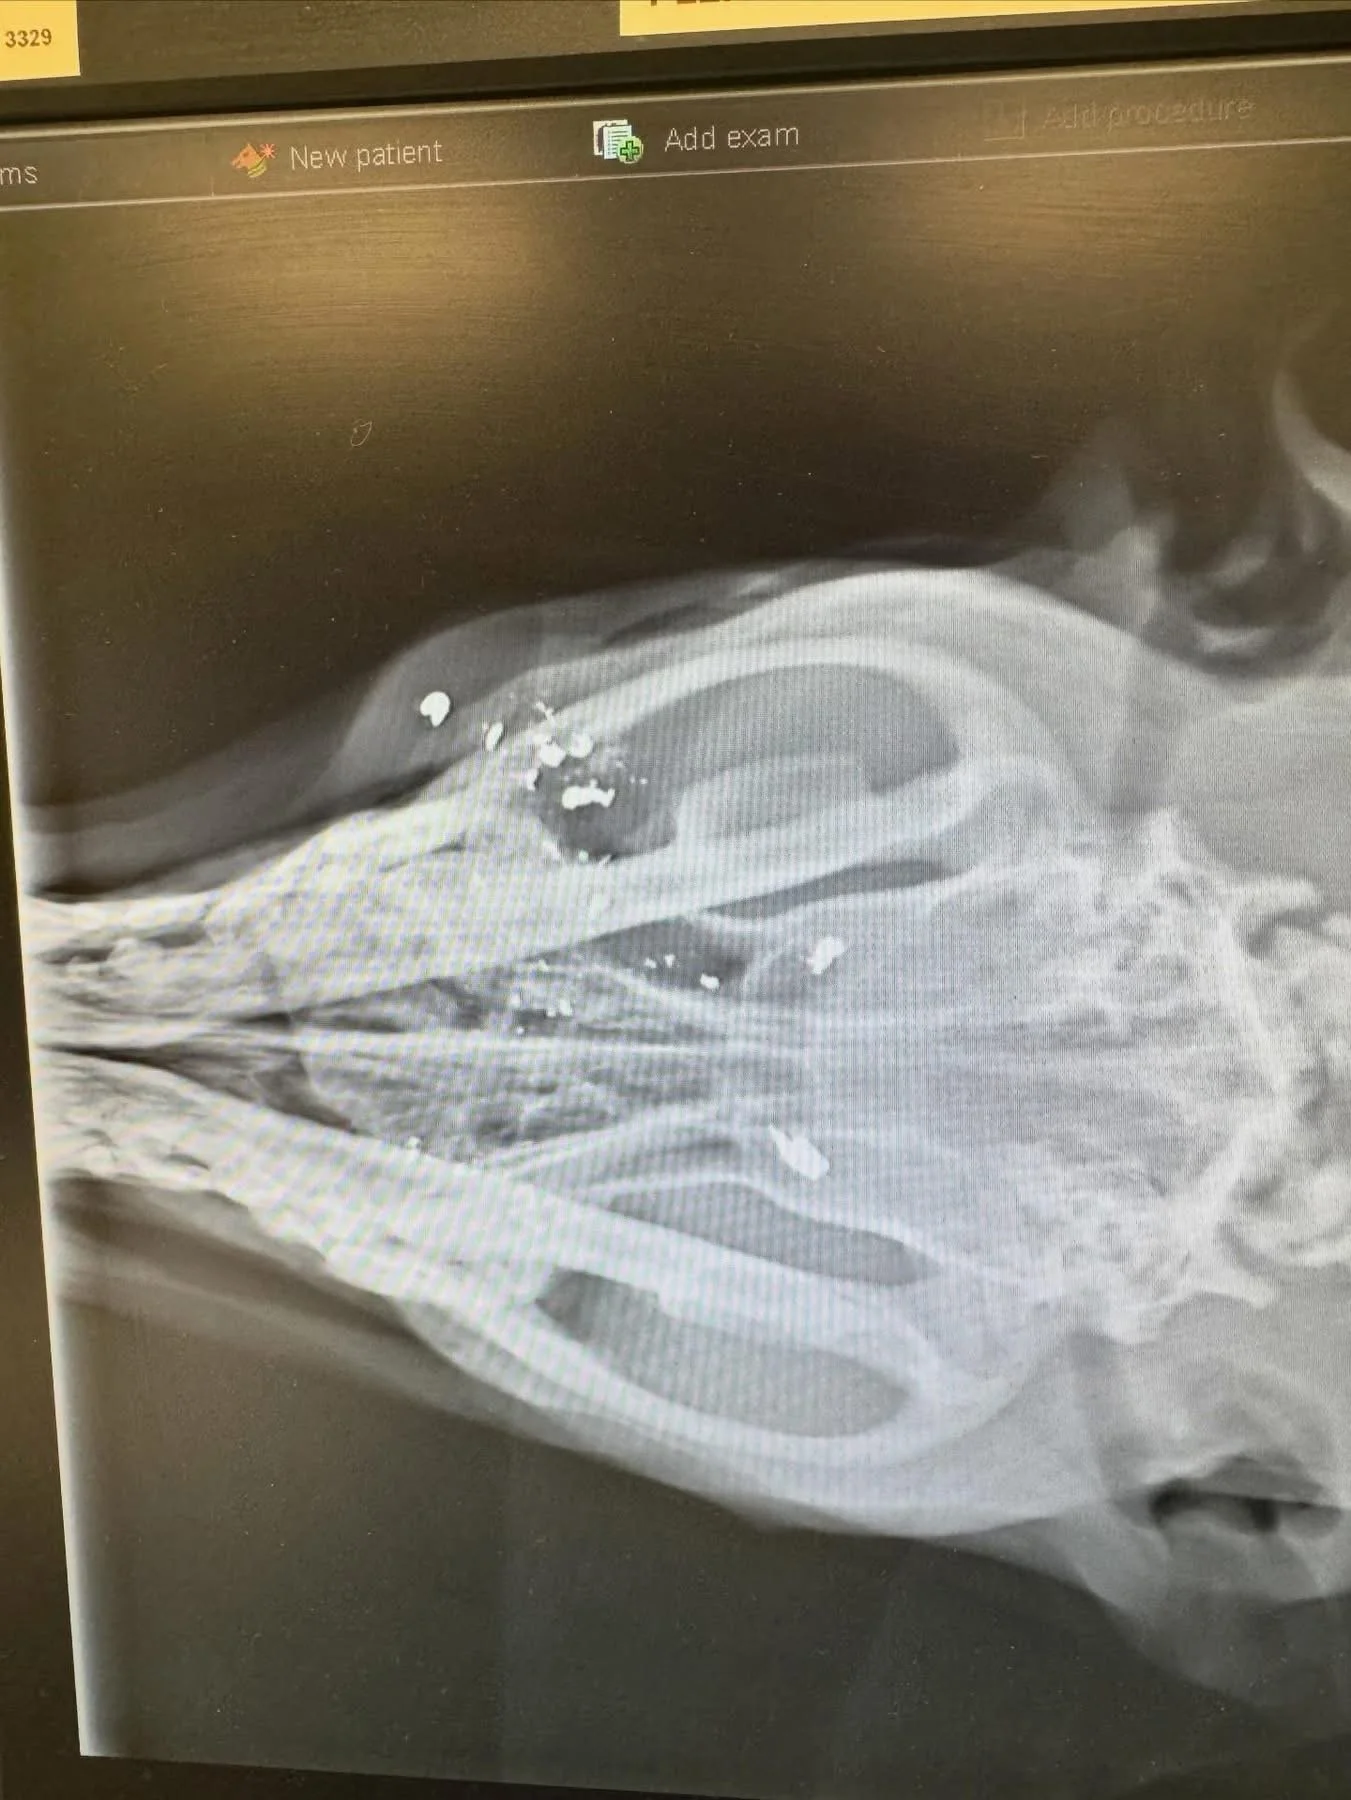

We finally got her safely into my car and dropped her off at the vet. The bullet had gone right through her cheek, tongue, and into her brain. Unfortunately, there’s not much we can do except strong pain medication, antibiotics, and hope 🙏 for a positive outcome.